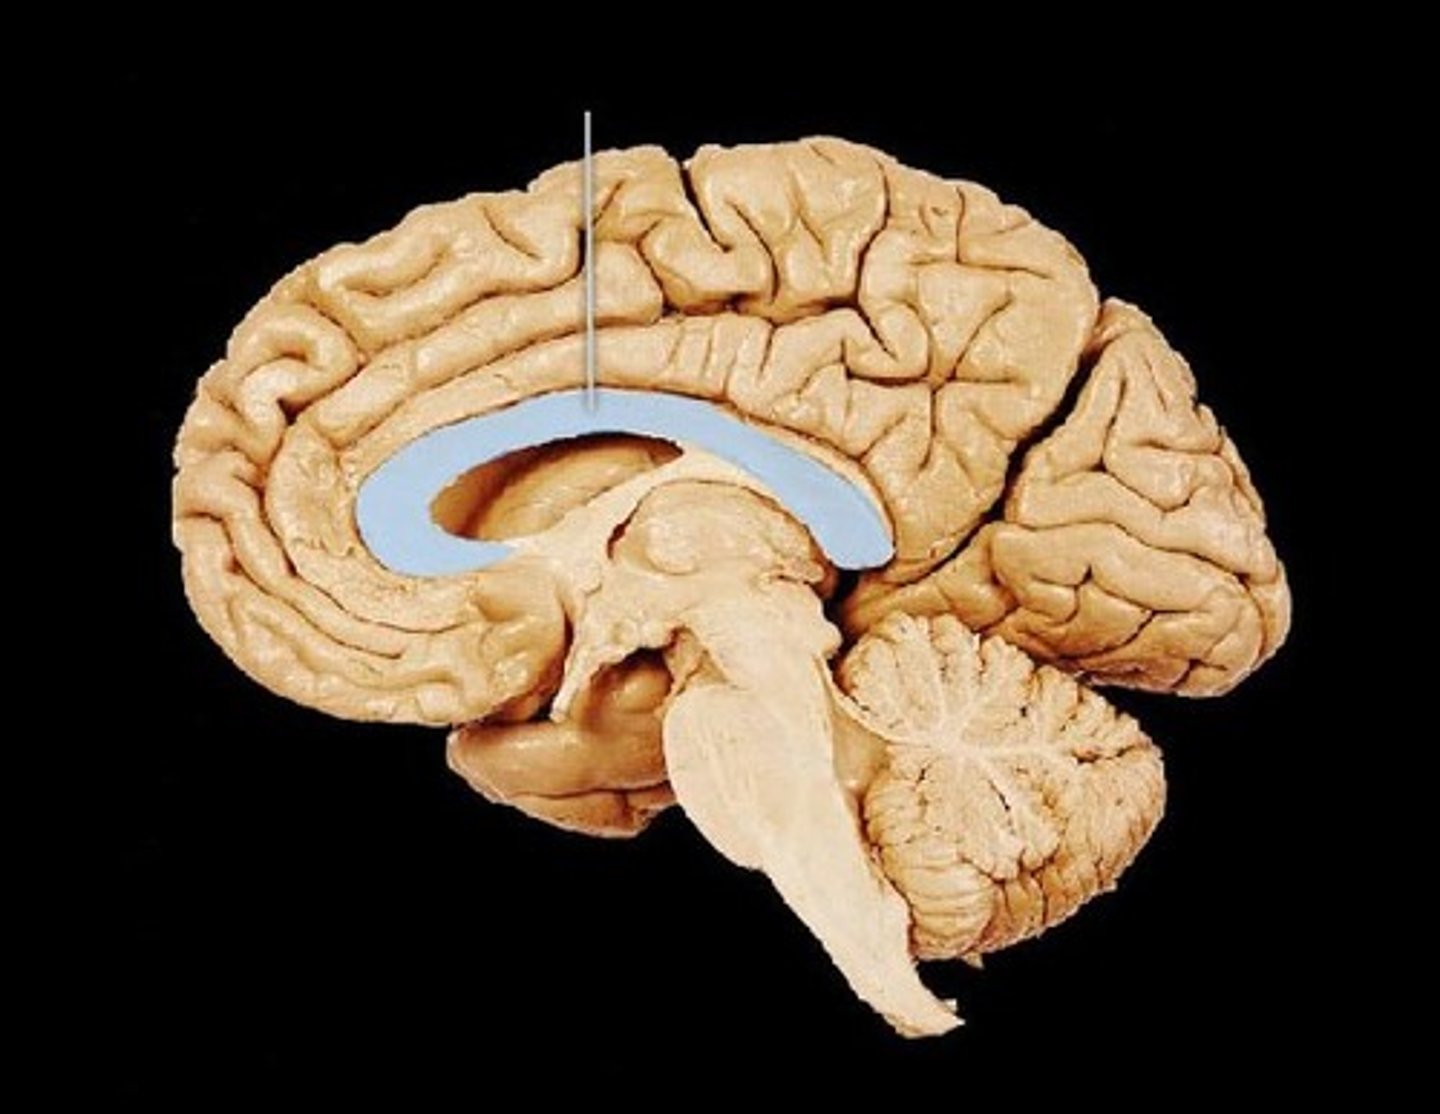

corpus callosum

broad band of white matter containing axons that extend between the cerebral hemispheres

commissural tracts of white matter

conducts nerve impulses one cerebral gyri to corresponding gyri in the other cerebral hemisphere.